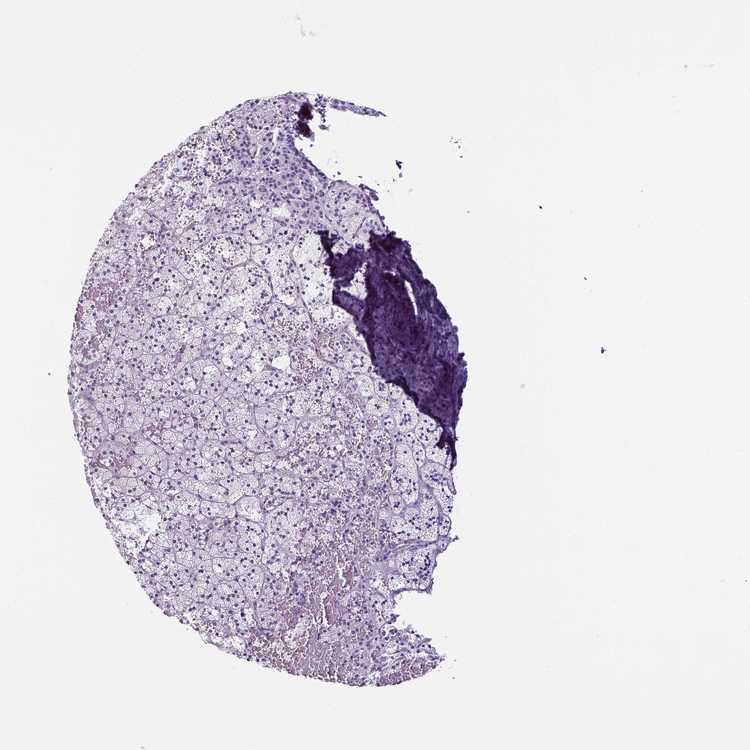

ADRENAL GLAND - Antibody stainingi

Antibody staining in the annotated cell types in the current human tissue is reported as not detected, low, medium, or high, based on conventional immunohistochemistry profiling in selected tissues. This score is based on the combination of the staining intensity and fraction of stained cells.

Each image is clickable and will lead to virtual microscopy that enables deeper exploration of all samples and also displays staining intensity scores, fraction scores and subcellular localization as well as patient and tissue information for each sample.

Antibody HPA001042Antibody HPA029543Antibody CAB023669Antibody CAB062562Antibody CAB067751Antibody CAB068229Antibody CAB068230Antibody CAB068231

Glandular cells Not detectedNot detectedNot detectedNot detectedNot detectedNot detectedNot detectedNot detected